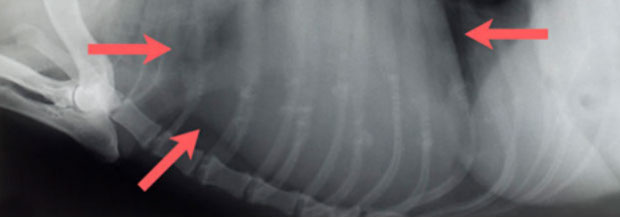

Mehrfachfrakturen nach Autounfall mit Lähmung der Hinterextremitäten, Hund